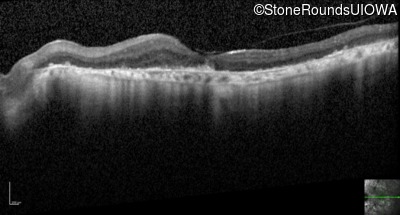

Optical Coherence Tomography - Right - 3/120

Exemplar / OCT Stack

OCT Stack